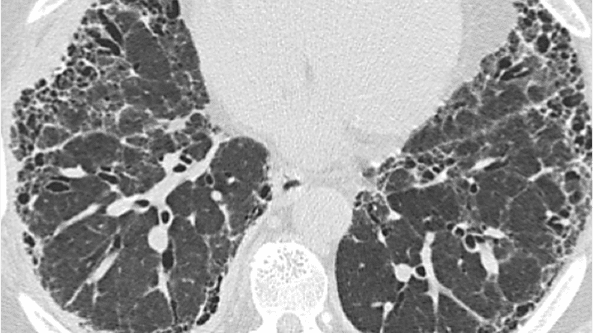

ASPECT DE FAGURE DE MIERE

Caracteristici

• Spații aeriene chistice grupate, cu pereți bine delimitați, măsurând 2–10 mm în diametru, ajungând uneori la 25 mm, de obicei în regiunile subpleurale

Semne asociate cu aspectul de fagure de miere

• Reticulații intralobulare

• Bronșiectazii de tracțiune și bronșiectazii

• Pierderea în volum a lobului pulmonar

• Distorsiunea scizurii pulmonare

Aspect de fagure de miere subpleural care formează mai multe straturi de chisturi la un bărbat de 73 de ani cu UIP